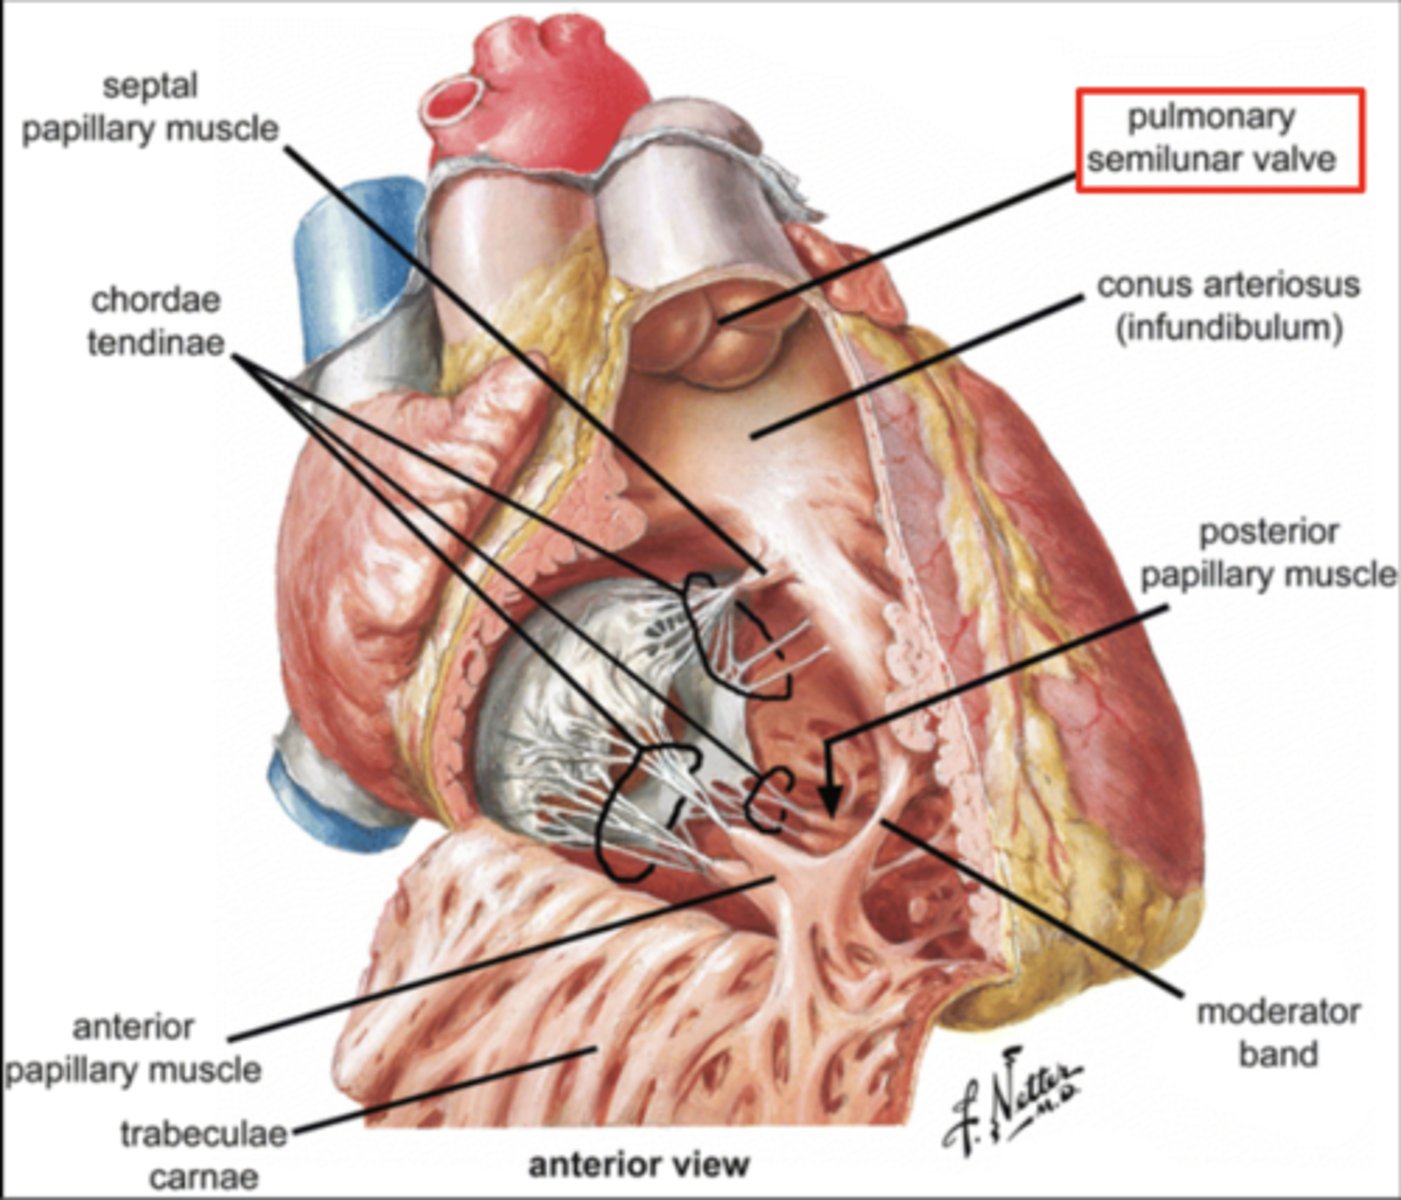

Describe the two portions of the medial/septal face/wall of the right ventricle.

infundibulum or outflow region or conus arteriosus (smooth and membranous)

trabeculae carnae (muscular and irregular)

What is the septomarginal trabeculae (or moderator band)?

Part of the conduction system of the heart.

electrical waves pass through this band to reach the papillary muscles.

What are the positions of the pulmonary valve cusps?

Anterior

Right

Left

What role does the moderator band play in the conduction system?

Allows the wave to reach the papillary muscles, inducing their contraction simultaneously with that of the ventricles.

REMEMBER: PAPILLARY MUSCLES ACT THROUGH THE CHORDAE TENDINAE TO CONTROL THE TRICUSPID AND MITRAL VALVES.